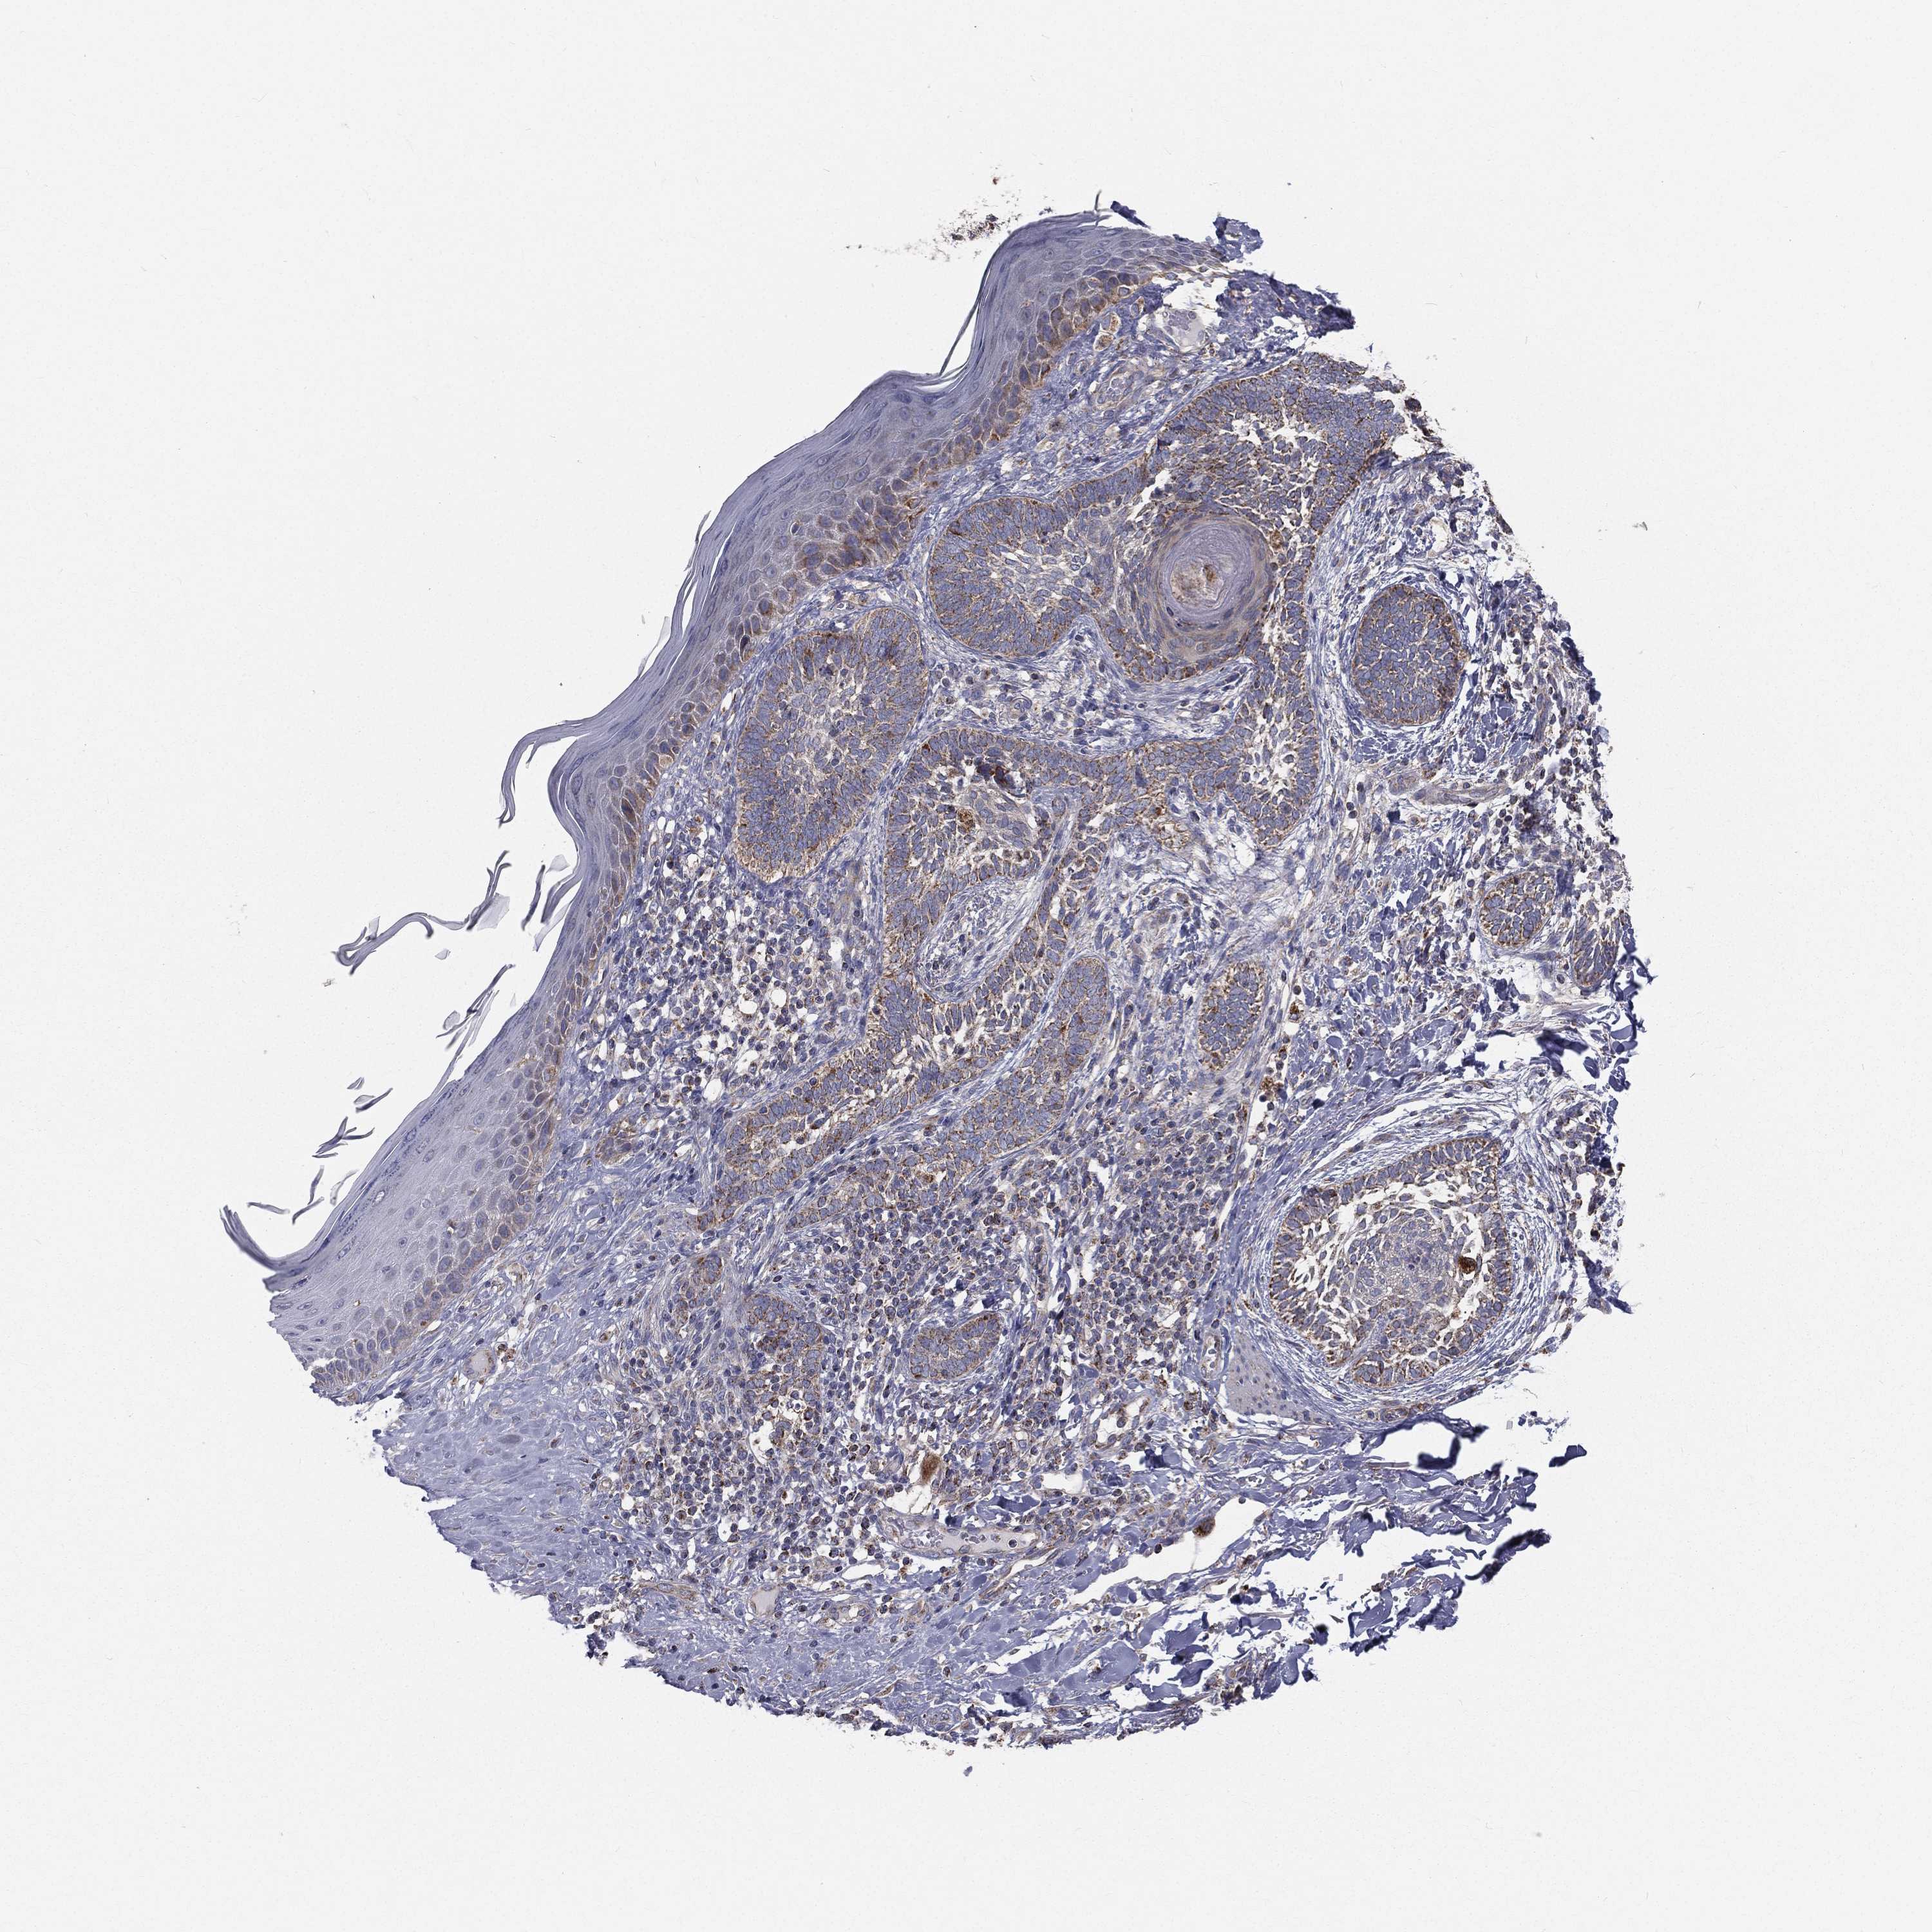

Basal cell and squamous cell cancer

SKIN CANCER - Protein expressioni

A mouse-over function shows sample information and annotation data. Click on an image to view it in a full screen mode. Samples can be filtered based on level of antibody staining by selecting one or several of the following categories: high, medium, low and not detected. The assay and annotation is described here.

Each image is clickable and will lead to virtual microscopy that enables deeper exploration of all samples and also displays staining intensity scores, fraction scores and subcellular localization as well as patient and tissue information for each sample.

Antibody HPA039588

Antibody HPA043888

Basal cell carcinoma

Squamous cell carcinoma, NOS